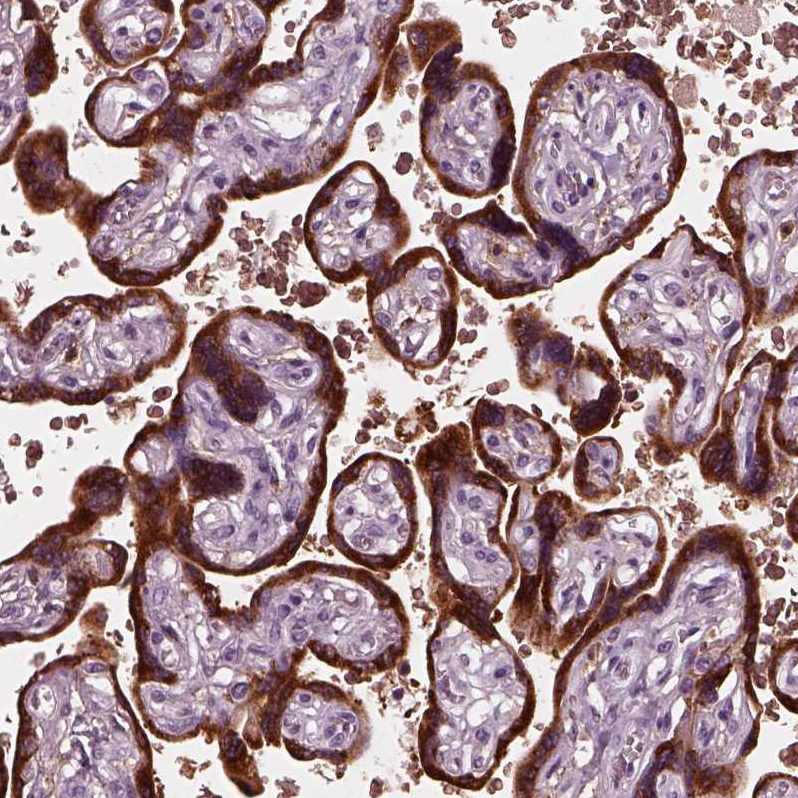

Immunohistochemistry analysis in human placenta and prostate tissues using HPA029698 antibody. Corresponding CGA RNA-seq data are presented for the same tissues.